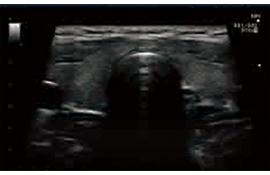

臨床圖例